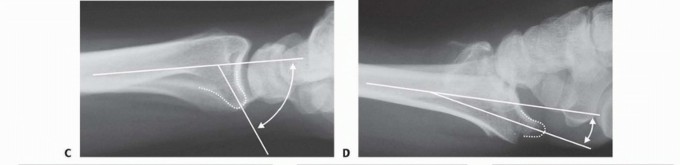

TECH FIG 5 • Volar rim fixation with small fragment plate. A,B. Shear fracture of volar rim with volar instability pattern. C,D. Fixation with small fragment plate.

TECH FIG 6 • Volar rim fixation with a volar buttress pin. A,B. Articular fracture with axial instability pattern of volar rim. C. Insertion of Kirschner wires. D. Cutting and inserting legs. E. Reduction of teardro (continued) 85

TECH FIG 6 • (continued) F. Completed fixation. G,H. Volar buttress pin fixation to control rotational alignment of volar rim fragment. Fine-tune the reduction and fix it proximally with a minimum of two screws and washers ( TECH FIG 6F-H). If needed, a blocking screw can be placed just proximal to the end of the buttress pin to prevent shortening of the fragment. Alternatively, a wire plate can be used to secure the implant proximally. Volar Hook Plate Fixation Volar hook plates are useful alternative to volar buttress pins for fixation of unstable volar rim fragments, particularly for small distal fragments associated with axial instability patterns of the volar rim or volar instability patterns associated with volar shear fractures. Expose and reduce the volar rim fragment according to the technique described for the volar buttress pin. If possible, provisionally hold the reduction with a Kirschner wire in the radial and ulnar border. Position and insert a 0.045-inch Kirschner guidewire distally down the center of the teardrop along the intended path of the hooks of the plate. Confirm the position with the C-arm. For hard bone, place a volar hook plate drill guide over the guidewire, and predrill the cortex for insertion of the hooks. In osteoporotic bone, this step may not be necessary. Insert the volar hook plate over the guide pin and seat into the distal fragment ( TECH FIG 7A-C). Place a distal locking peg of appropriate length after predrilling with a fixed-angle peg guide. Fix the plate proximally with standard bone screws.